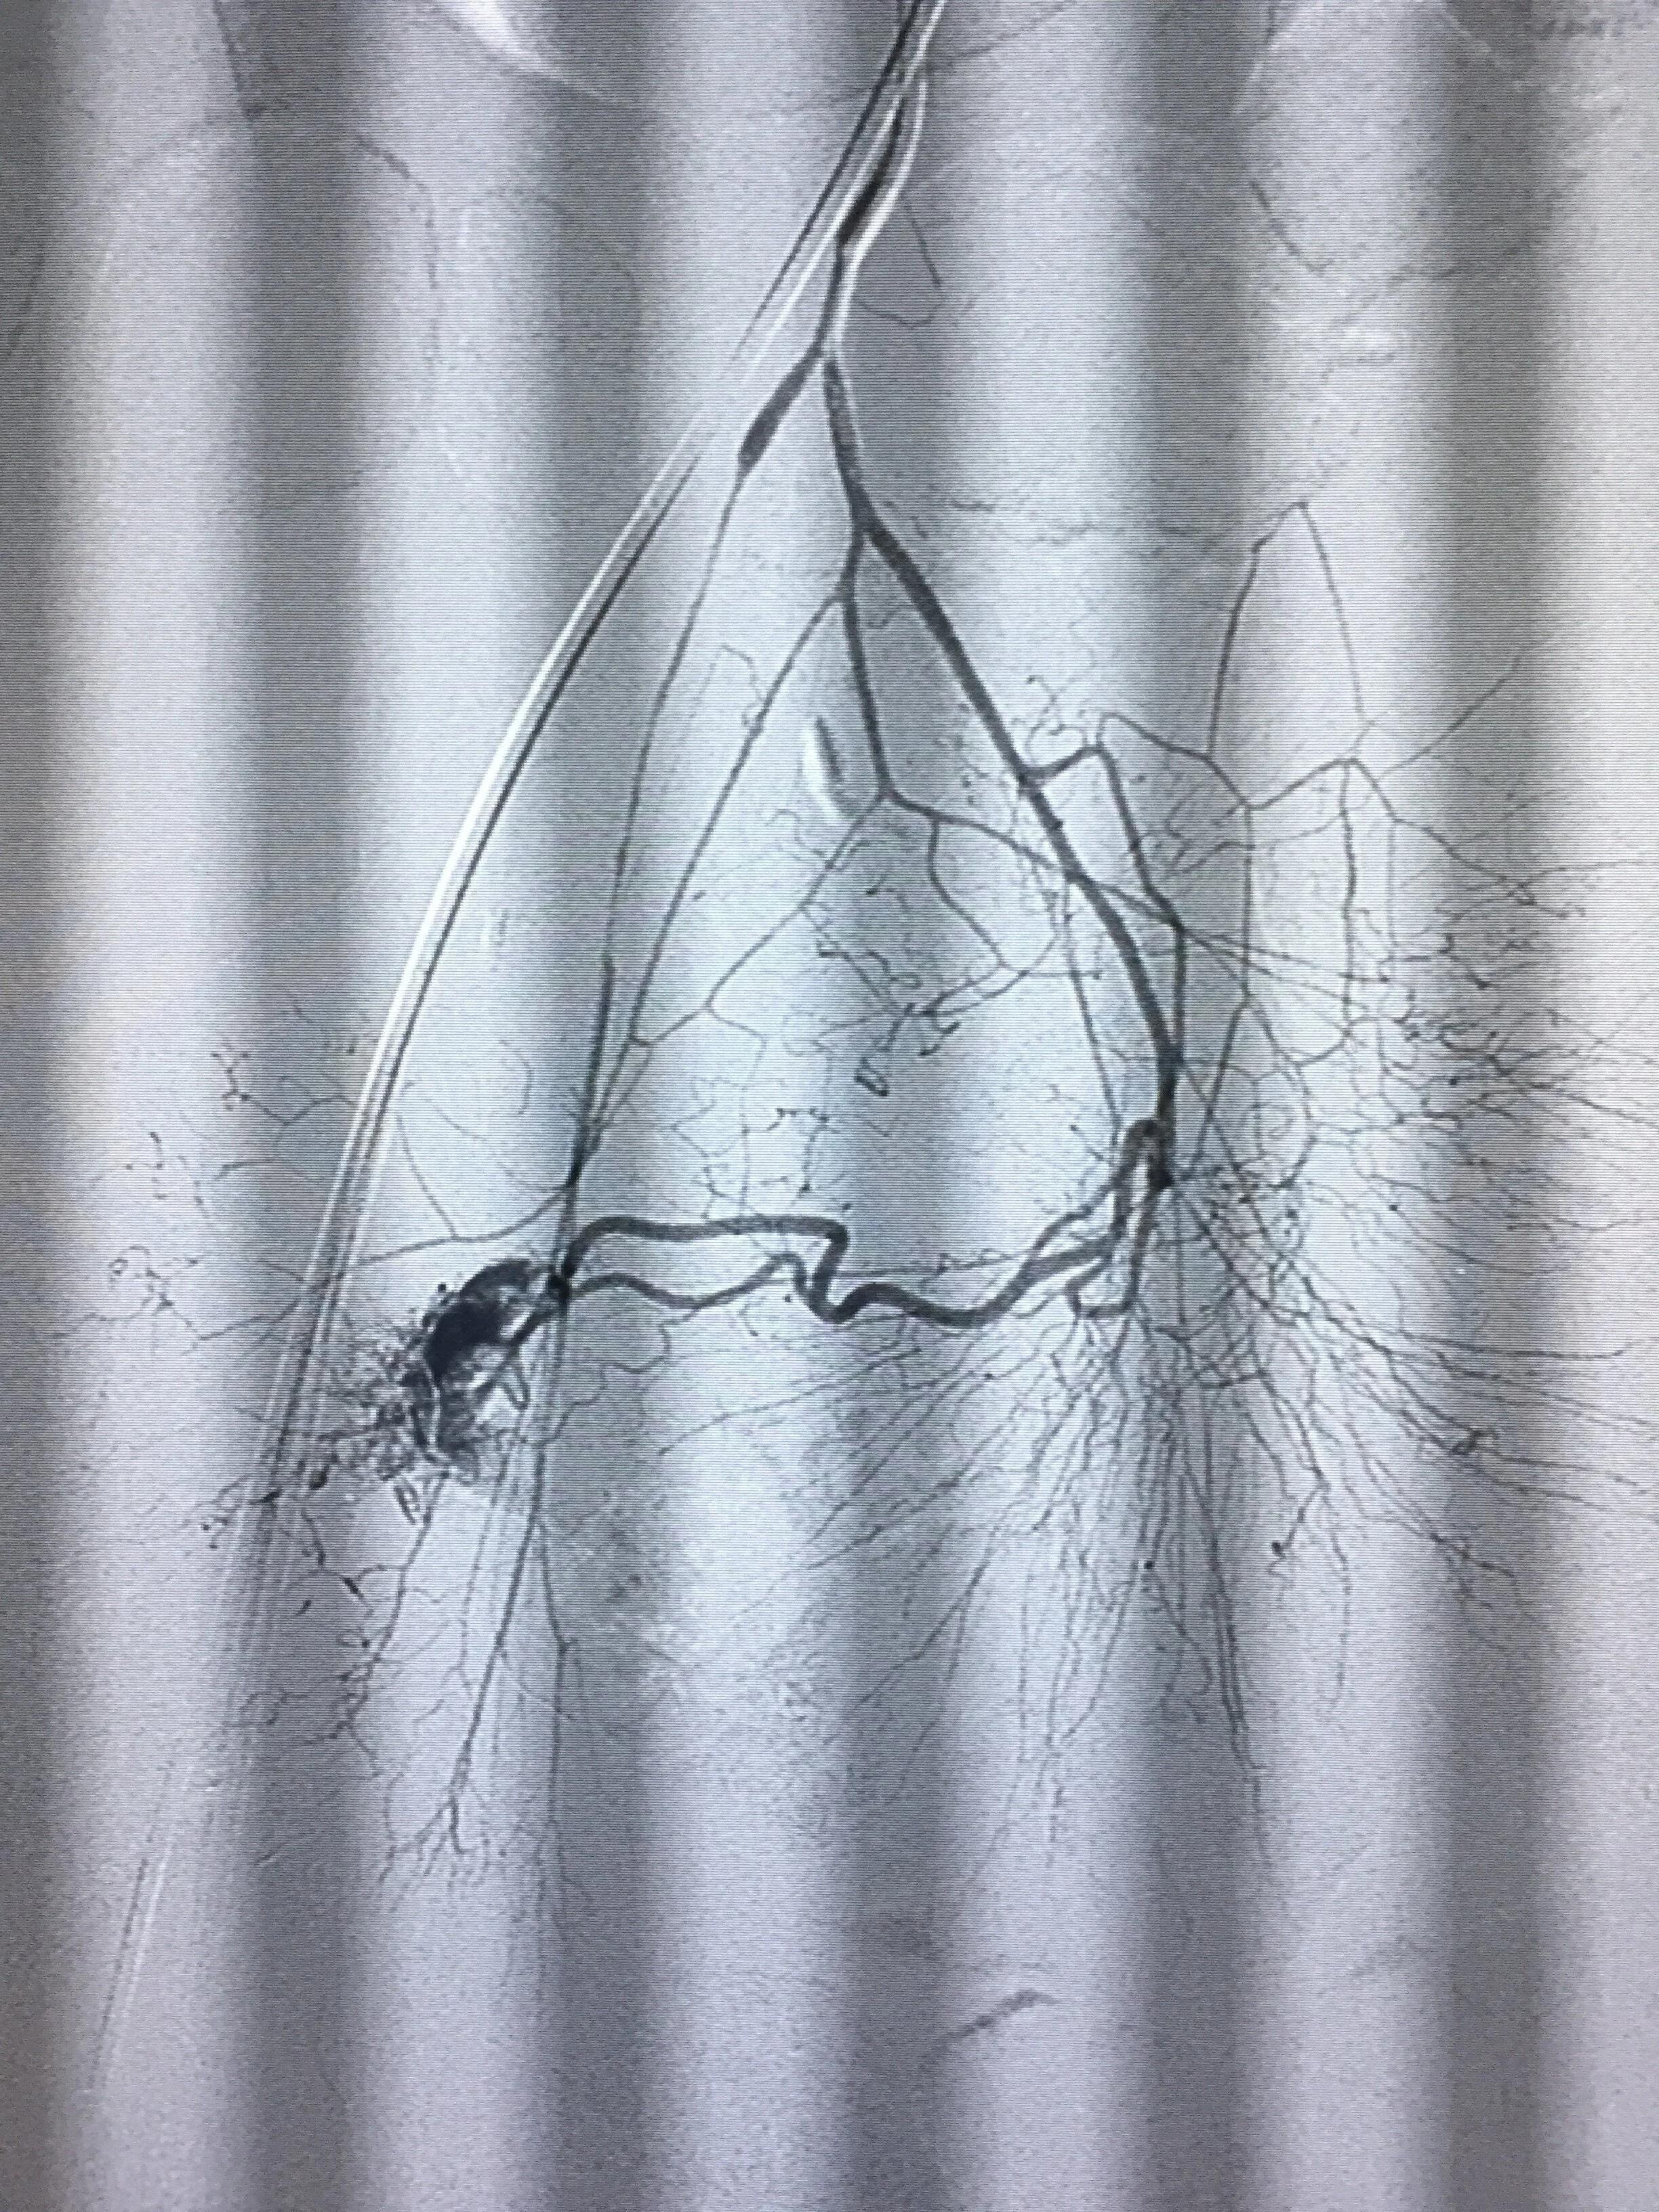

Arteriograma de arteria iliac interna, enseñando una malformación vascular arteriovenosa de flujo rápido. Estudio preliminar antes de embolización con cianoacrilato.